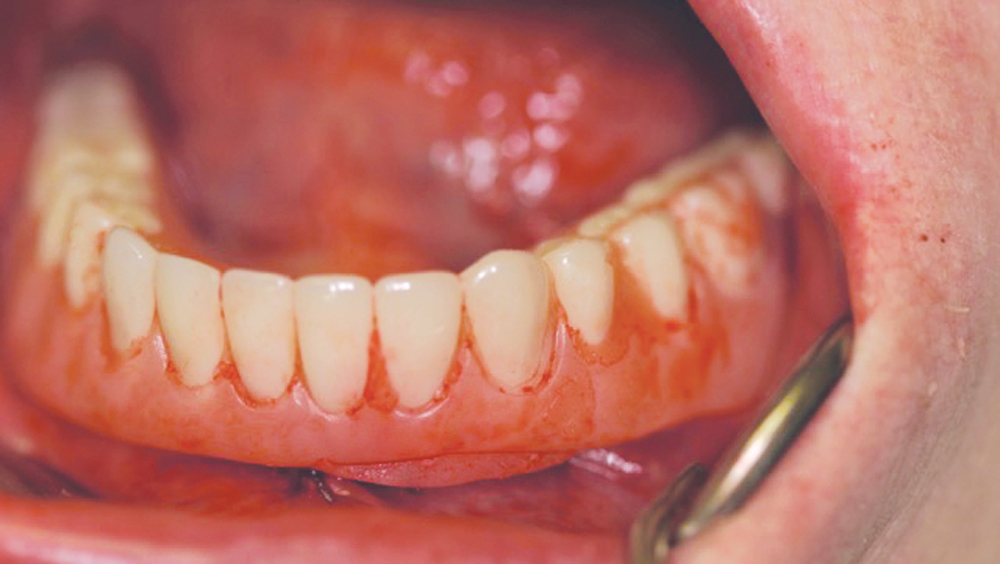

Patients who present with terminal dentition commonly suffer from discomfort, poor dental function and low self-esteem as a result of their condition. Immediate implant placement is a treatment option that offers instant, life-changing benefits for these patients while setting the stage for a predictable long-term outcome. In the presence of sufficient bone quality and volume, after atraumatically extracting the patient’s teeth, implants can be placed and a temporary appliance delivered, allowing the patient to walk out of the office with dramatically improved form and function in one appointment. This immediately enhances the patient’s quality of life and provides a significant “wow” factor for your practice.

The following case demonstrates how to immediately place implants in full-arch indications. By properly positioning the implants, maximizing primary stability and providing the most durable restoration possible, the short- and long-term needs of the patient are addressed in an efficient, predictable manner.